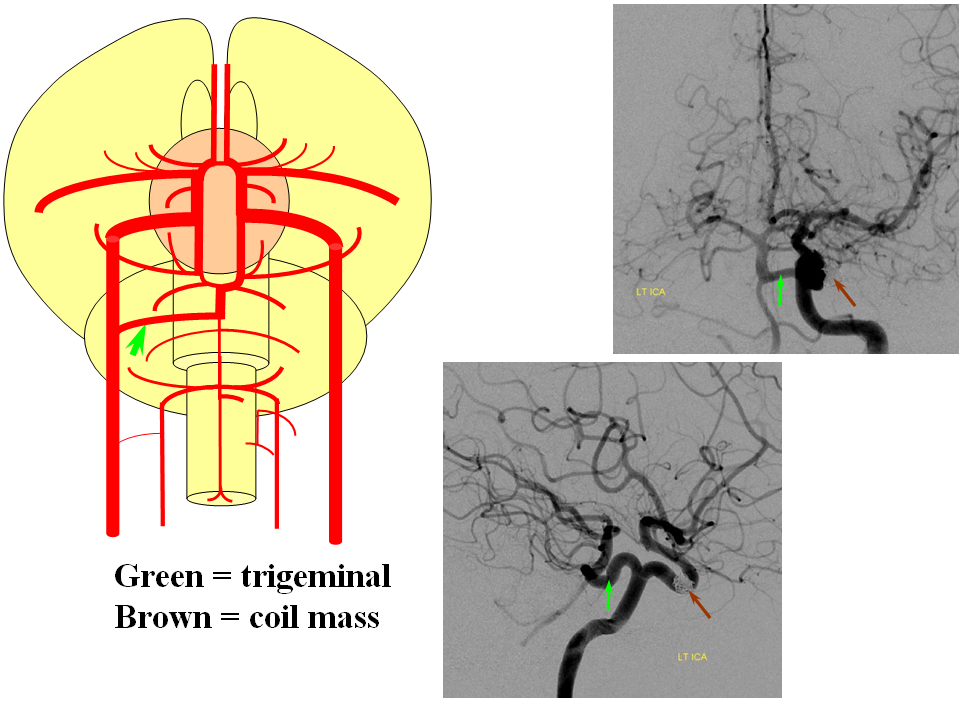

Here is an example, also found on the Neurovascular Evolution page; the “classic” trigeminal (green arrows) extends from the basilar trunk between the AICA and SCA, to the MHT, and is associated in this case with hypoplasia of the PCOM. Essentially all vascular variants are associated with a slightly increased incidence of brain aneurysms, as evidenced by the coil mass (brown arrows)

Here is a CT of the same case, showing the trigeminal as well as another variant, the accessory MCA (purple arrows), also discussed in greater detail on the Neurovascular Evolution page.